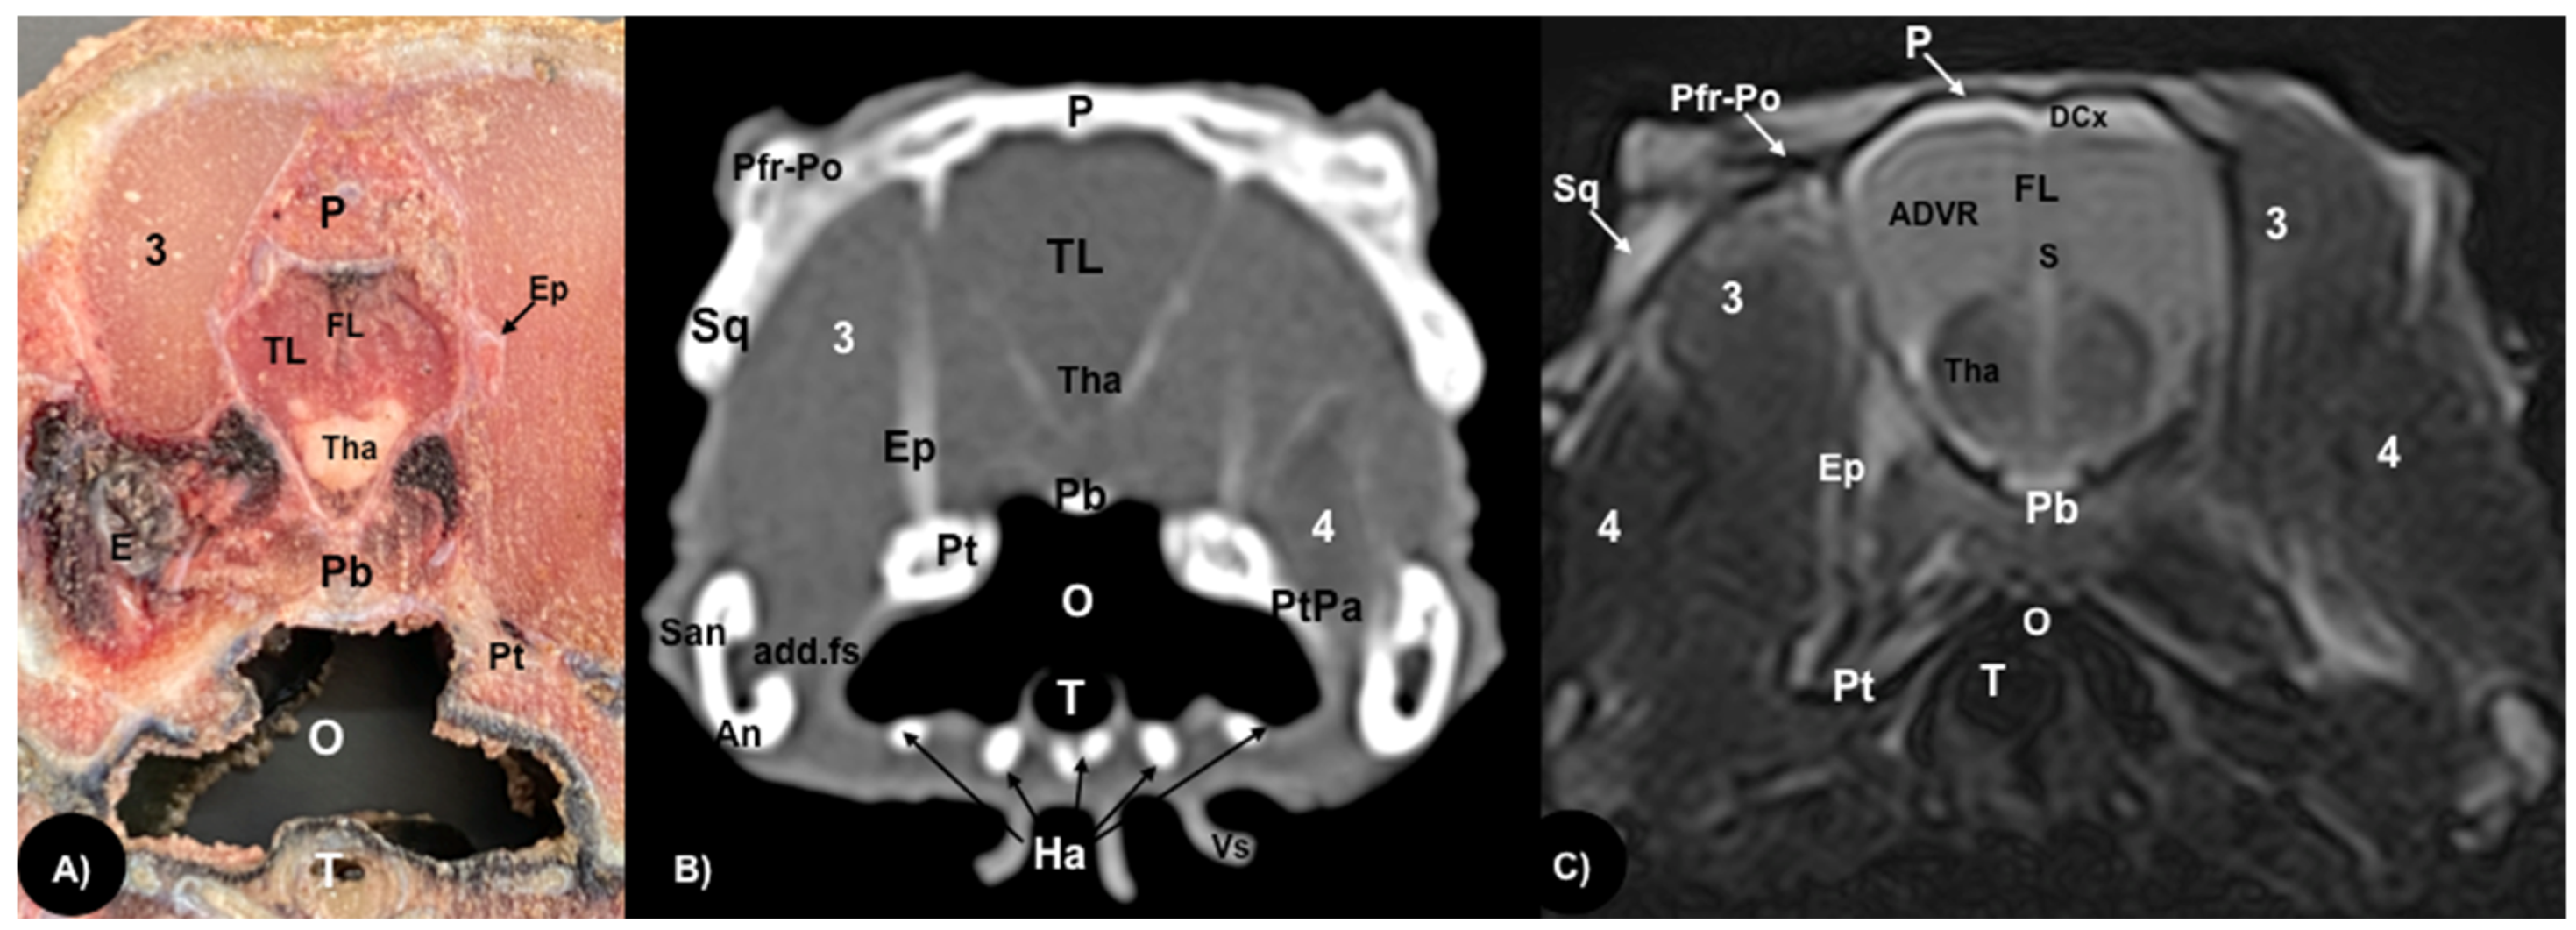

Figure 5.

Transversal gross-section (A), CT bone window (B) and MRI in T2W (C), images of the head of rhinoceros iguana at the level of the anterior dorsal ventricular ridge (ADVR) corresponding to line IV in Figure 1. P: Parietal bone. Pfr-Po: Postfrontal-Postorbital bone. Sq: Squamousal bone. E: Eyeball. TL: Telencephalon. FL: Fissura longitudinalis cerebri. Tha: Thalamus. ADVR: Anterior Dorsal Ventricular Ridge. DCx: Dorsal cortex. 3: Musculus adductor mandibulae externus medialis. 4: Musculus adductor mandibulae externus superficialis. Pb: Parabasisphenoid bone. Pt: Pterygoid bone. Ep: Epipterygoid bone. PtPa: Pterygoid-palatine processes. add.fs: Adductor fossa. An: Angular bone. San: Surangular bone. Ha: Hyoid apparatus. O: Oral cavity. T: Trachea. Vs: Ventral spines.

Different structures belonging to the central nervous system were visualized by anatomical gross-sections. Therefore, we identified the brain (telencephalon) and the two telencephalic hemispheres (Figure 4A and Figure 5A) separated by the fissura longitudinalis cerebri (Figure 5A), the diencephalon (thalamus) (Figure 4A and Figure 5A), the dorsal part of the mesencephalon with the two caudal colliculus (Figure 6A) and the ventral part of the cerebellum with the nodule, covering part of the fourth ventricle, as well as the ventral surface of the brainstem (myelencephalon) (Figure 6A). These sections were also helpful for the observation of the olfactory bulb that showed an extracranial location, ventral to the frontal bones, and coursed between the two eyeballs (Figure 3). In addition, these sections allowed the description of structures of the eyeball, identifying the cornea, the sclera, the retina, the vitreous humor, the lens, as well as associated structures such as the interorbital septum and the orbital sinus (Figure 3A and Figure 4A). In addition, these transverse sections allowed the identification of structures belonging to the oral cavity such as the tongue (Figure 2A) and other structures such as the larynx, with the corniculate tubercles of the arytenoid cartilage, the thyroid cartilage, and the laryngeal ventricle (Figure 3A), as well as of different structures of the nasal cavity such as the nasal glands that filled almost the entire cavity, the conchal grooves and the stammteil located laterally to the nasal septum (Figure 2A). Adjacent structures such as the trachea and the nasopharynx were also well identified (Figure 4A, Figure 5A and Figure 6A). Furthermore, most bony structures that form the neurocranium were observed, such as the pterygoid, frontal, postfrontal-postorbital, parietal, supraoccipital, basioccipital, exoccipital, otoccipital, parabasisphenoid and sphenoid bones (Figure 3A, Figure 4A, Figure 5A and Figure 6A), as well as those that form the splanchnocranium such as the nasal, vomer, palatine and maxillary bones (Figure 2A and Figure 3A) and also the medial horn located dorsal to the nasal bone (Figure 2A), the mandible, with the dentary bone (Figure 3A), and the hyoid apparatus, visualizing the central body of the hyoid arch, between the lateral branches of the dentary bone (Figure 3A). Rostromedially to the two dentary bones, we identified different muscles related to the hyoid apparatus such as the musculus genihyioideus, hyoglossus and intermandibularis (Figure 2A and Figure 3A). In the following sections, we also observed the muscle groups corresponding to the mandibular musculature (we were not able to dissect them, and therefore they were treated as a group), including the pterygoideus, omohyoideus, sternohyoideus, ceratohyoideus, adductor mandibulae externus medialis and its homonym superficialis (Figure 4A and Figure 5A).

Regarding the neurocranium, the CT images allowed us to distinguish bone structures such as the prefrontal, frontal, postfrontal-postorbital, parietal, squamosal, quadrate, epipterygoid, pterygoid, basioccipital, exoccipital, otoccipital and parabasisphenoid bones (Figure 3B, Figure 4B, Figure 5B and Figure 6B); related to the splanchnocranium, we observed the nasal, premaxilla, maxilla, septomaxilla, vomer, jugal and palatine bones, and the nasal septum (Figure 2B, Figure 3B, Figure 4B, Figure 7B and Figure 8B); the mandible structures such as the dentary, angular, surangular, coronoid and articular bones (Figure 2B, Figure 3B, Figure 4B, Figure 5B and Figure 6B) and the hyoid apparatus (Figure 2B, Figure 3B, Figure 4B, Figure 5B and Figure 6B). CT scanning and post-processing transverse images showed the relation between the different bones that form the head of the rhinoceros iguana, the junction of the nasal and the prefrontal bone, as well as that of the parietal bone with the postfrontal-postorbital bone (Figure 2B and Figure 4B), and the palatine and quadrate processes of pterygoid bone (Figure 5B and Figure 6B respectively). The prominent medial horn was identified dorsal to the nasal bone with soft-tissue attenuation and a thin, lamellar-shaped mineral structure bordering it regularly on its most external aspect (Figure 2B).

Concerning the nasal cavity, the transverse CT image showed the nasal glands as symmetrical bilateral structures, with regular and well-defined margins, located on both sides of the nasal cavity and with soft tissue attenuation (Figure 2B). Moreover, those structures with intraluminal gas content such as the nasal conchal recess (Figure 2B), oral cavity, nasopharyngeal duct, trachea, adductor fossa (Figure 4B) and the otic cavity (Figure 6B) were identified with this technique, appearing with a vacuum effect. In addition, there were areas of soft tissue attenuation medial to the mandible and bilateral to the hyoid apparatus, compatible with the intermandibularis, genihyioideus and hyoglossus muscles (1 in Figure 2B and Figure 3B), the pterygoideus, omohyoideus, sternohyoideus and ceratohyoideus muscles (2 in Figure 4B), the adductor mandibulae externus medialis and superficialis muscles located, respectively, dorsomedially and ventrolaterally to the adductor fossa (3 and 4 in Figure 4B and Figure 5B).

3.3. Magnetic Resonance Imaging (MRI)

The soft structures of the iguana’s head, such as the central nervous system as well as the eyeball’s structures (vitreous humor and lens), the oral cavity with the tongue and the masticatory muscles, showed an accurate visualization using MRI (Figure 2C, Figure 3C, Figure 4C, Figure 5C and Figure 6C). Therefore, an increased volume of both eyeballs in proportion to the size of the head was seen in all sequences (Figure 3C and Figure 7B). As in CT, the structures with gas content (Figure 2C and Figure 6C) appeared with a vacuum effect, being hypointense in all sequences. The nasal glands were bilaterally symmetric, with regular and well-defined margins, located on both sides of the nasal cavity, being iso/hyperintense in T1W and T2W sequences, compared to the encephalic grey matter (Figure 2C and Figure 4C). In contrast, the medial horn appeared hypo/isointense on T1W and T2W sequences concerning the white matter and with mild differentiation of the external bony cortex in relation to the white matter (Figure 2C).

In contrast to the CT images, the bone junctions were not distinguishable on MRI, but those bones that formed the neurocranium, such as the frontal, postfrontal-postorbitary, parietal and supraoccipital bones were identified (Figure 3C, Figure 4C, Figure 5C, Figure 6C and Figure 8B). The cranial musculature was found isointense concerning the thalamus in T2W. This technique enabled a better resolution to identify the muscle groups already mentioned (Figure 2C, Figure 3C, Figure 4C and Figure 5C). In the transverse planes of the encephalon, the cerebral cortex was observed slightly more hyperintense than the white matter, which was more hypointense in T2W sequences (Figure 4C). The diencephalic region (Figure 4C, Figure 5C and Figure 8B) was hypointense (T2W) compared to the cerebral cortex (Figure 5C), showing the thalamus and hypothalamus (Figure 8B). The brainstem appeared hypo/isointense in T2W compared to the cerebral cortex, as well as presenting a markedly tortuous horizontal alignment (Figure 8B). Moreover, the caudal colliculus and the fourth ventricle were also displayed in excellent detail. In the rostral aspect of the telencephalon, we distinguished the dorsal pallium rostral part with its lateral and medial portions (Figure 4C). Interestingly, the dorsal MRI image was quite helpful to identify the olfactory bulb located extracranially, which extended rostromedially between the eyeballs (Figure 3C, Figure 7B and Figure 8B).